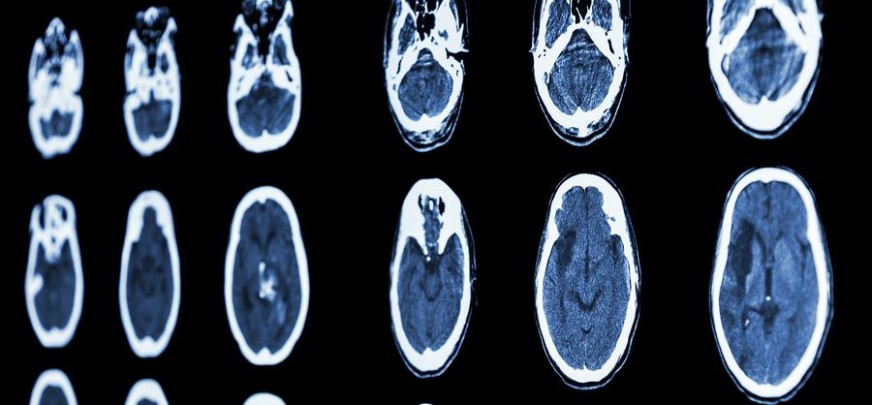

Could It Be Symptoms of Brain Hemorrhage? How to Recognize the Signs and Take Action

A brain hemorrhage comes in two forms. The first type involves bleeding directly in the brain and is usually caused by either a burst artery or when the head takes a hard hit in a fall. The second type occurs in the area between the brain and tissue covering it when, typically, a blood vessel expands and finally bursts. Blood from the burst vessel exerts pressure on the brain, cutting off oxygen to cells and, ultimately, killing them. Blood also irritates brain tissues, creating a bruise or bump called a hematoma, which can also place pressure on brain tissue.